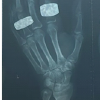

Introduction: For intra-articular distal radius fractures (AO Classification, type B2) with a displaced dorsal fragment, there remains much discussion on the fixation method for the dorsal fragment. To reduce the displaced dorsal fragment, we developed a new technique consisting of fenestration of the volar bone cortex, reduction using an intramedullary procedure, and fixation using a volar plate.

Case Report: We performed this surgical technique in 2 patients and achieved a good reduced position without much injury to the bone cortex at the site of volar plate placement. This surgical technique allows reduction of the dorsal fragment using an intramedullary procedure by only a volar approach, and, therefore, does not affect the dorsal soft tissue (extensor tendon). For intra-articular distal radius fractures, complete reduction of the articular surface is extremely difficult, and, in patients with a remaining gap on the articular surface, a variable angle locking screw system may be useful. In the 2 patients, the angle of the locking screw was adjusted to catch the displaced dorsal fragment, and adequate reduction and fixation could be achieved.

Conclusion: This technique, in which fenestration of the volar bone cortex allows a reduction procedure for the dorsal fragment, was useful for the reduction and fixation of the displaced dorsal fragment in distal radius fractures.